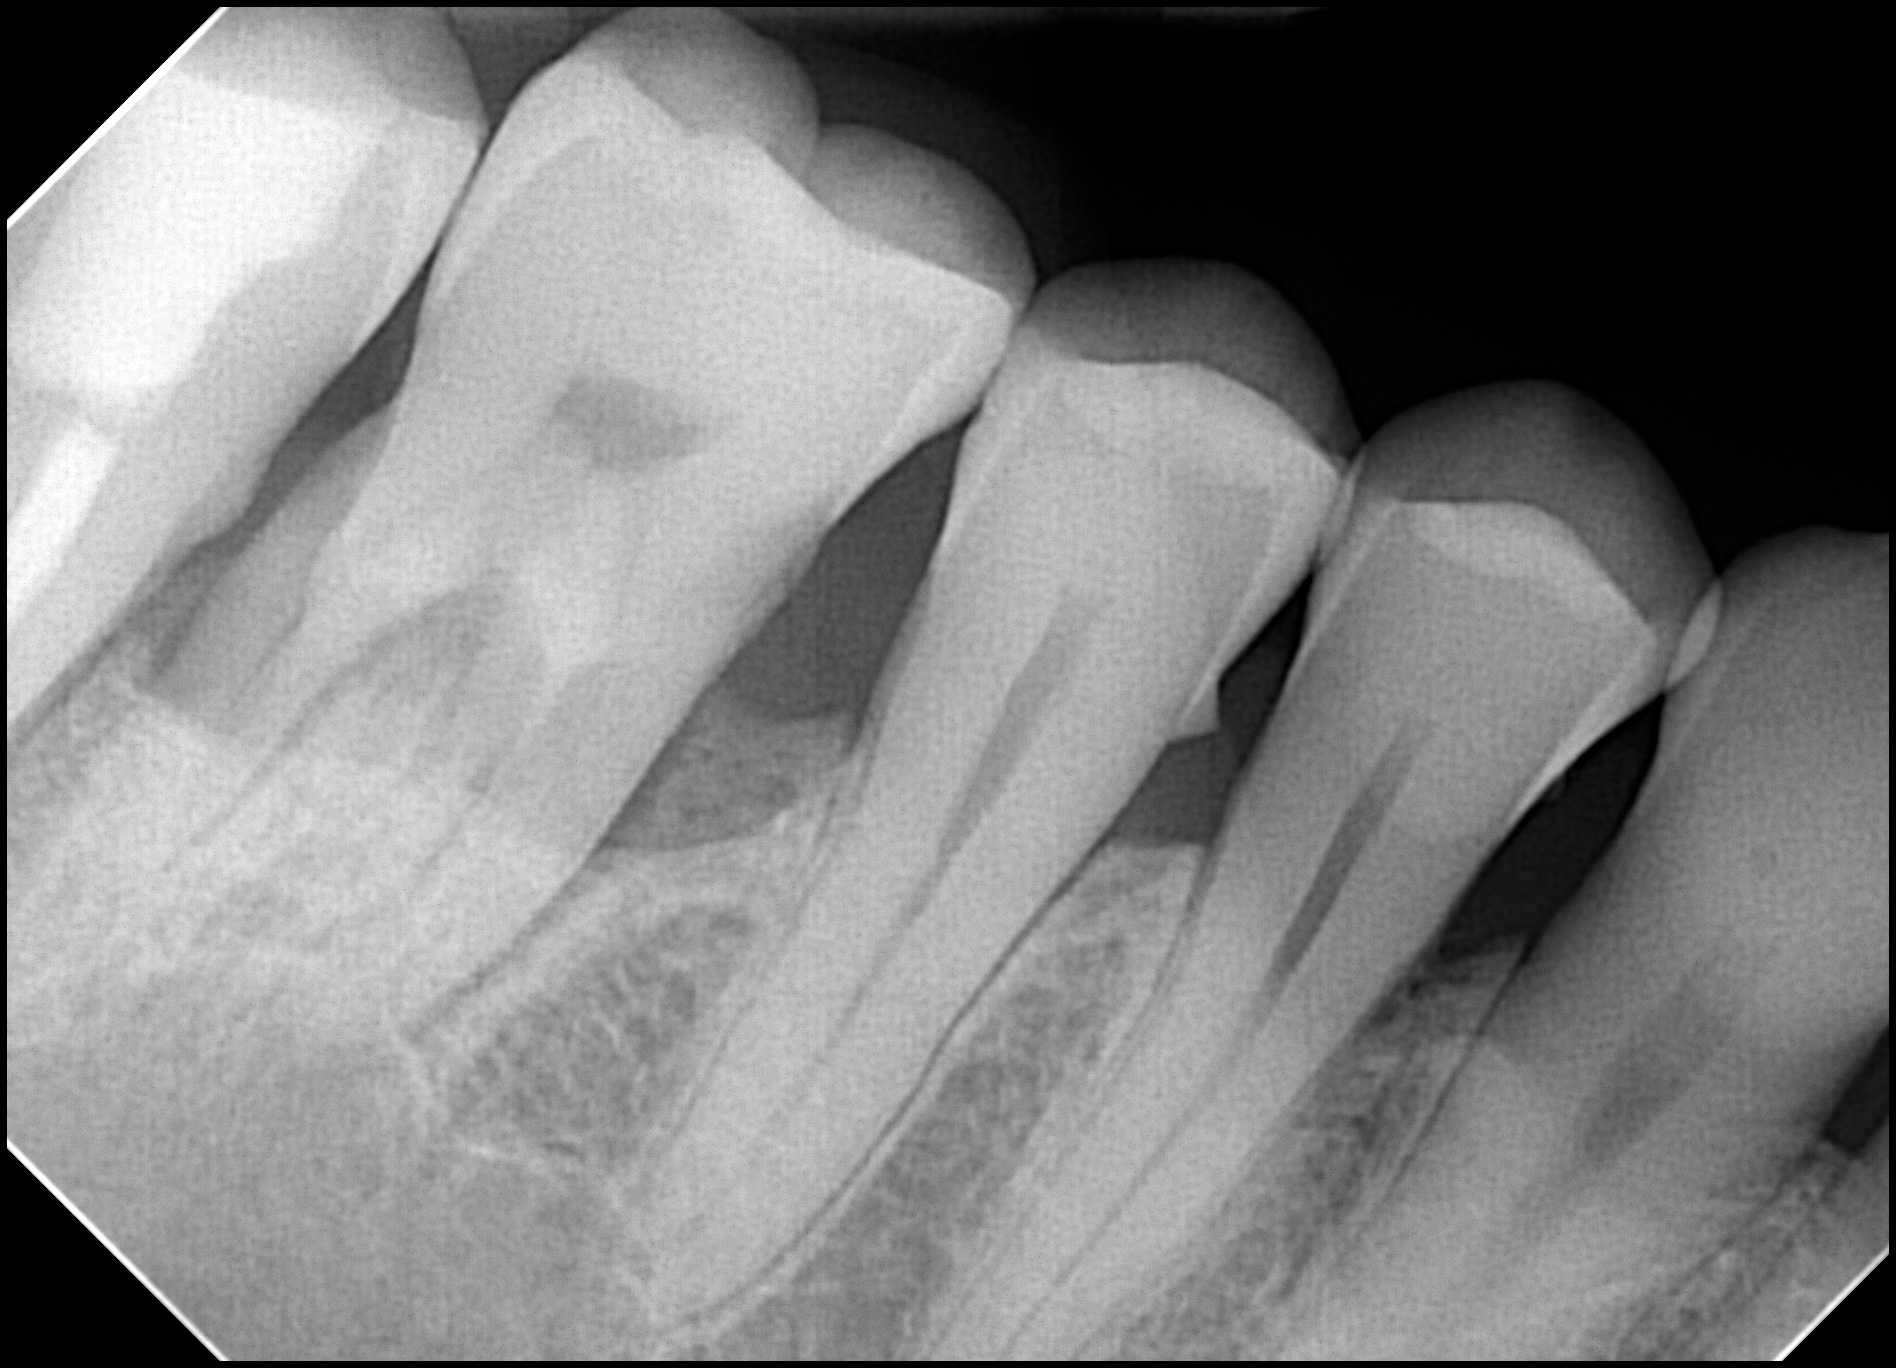

3 Key Differences Between Extraoral Dental Bitewings and Intraoral Dental Bitewings